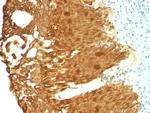

Cytokeratin 19 (KRT19) (Pancreatic Stem Cell Marker) Monoclonal Antibody (KRT19/799, KRT19/800)

Cytokeratin 19 is part of a subfamily of intermediate filament proteins and are characterized by a remarkable biochemical diversity, represented in human epithelial tissues by at least 20 different polypeptides. Cytokeratins range in molecular weight from 40-68 kDa and isoelectric pH between 4.9 - 7.8. The individual human cytokeratins are numbered 1 to 20. The various epithelia in the human body usually express cytokeratins which are not only characteristic of the type of epithelium, but also related to the degree of maturation or differentiation within an epithelium. Cytokeratin subtype expression patterns are used to an increasing extent in the distinction of different types of epithelial malignancies. The cytokeratin antibodies are not only of assistance in the differential diagnosis of tumors using immunohistochemistry on tissue sections, but are also a useful tool in cytopathology and flow cytometric assays. For example, cytokeratin 19 is not expressed in hepatocytes, therefore, it is useful in the identification of liver metastasis.